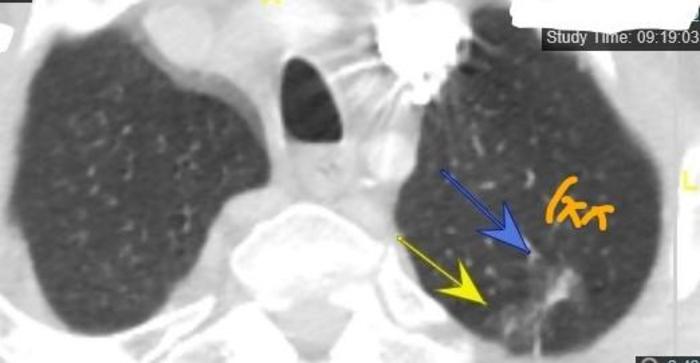

十三、海马形混合磨玻璃结节

这个磨玻璃结节有点像海里面的动物——海马。看起来很长。病理是浸润性腺癌,部分亚型为乳头亚型。